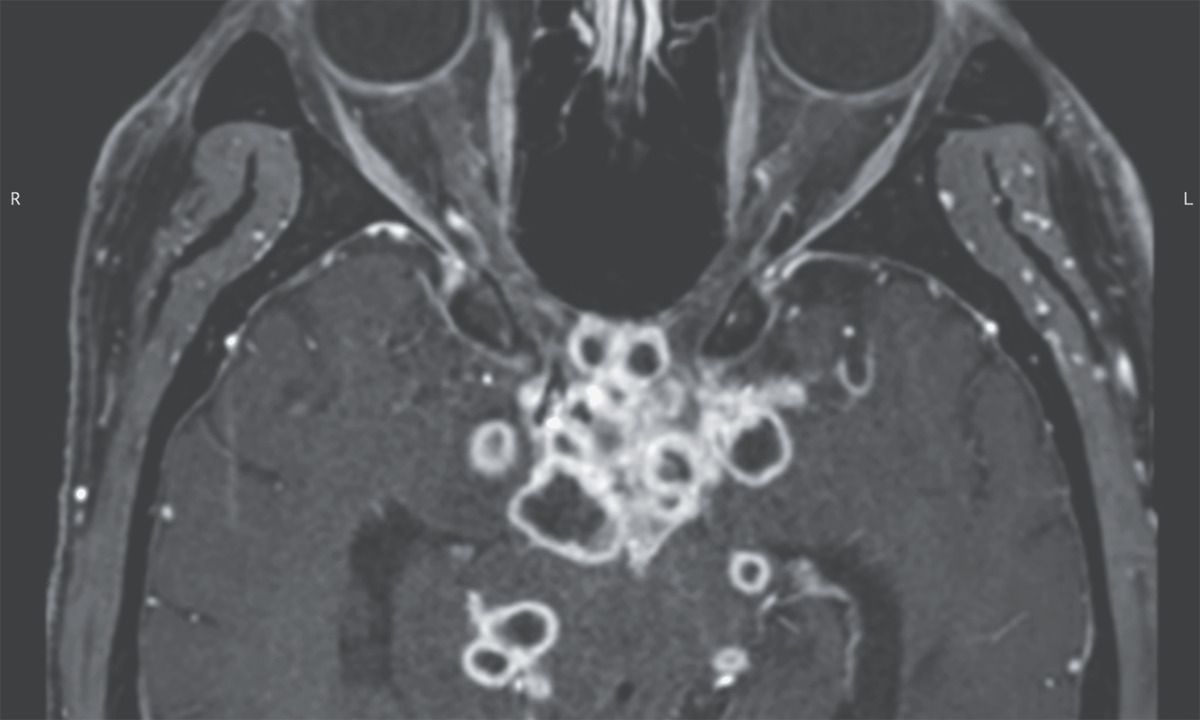

A 29-year-old man presented to the emergency department with a 1-week history of headache and blurry vision. Six weeks earlier, he had received a diagnosis of gastrointestinal tuberculosis and had begun antituberculosis therapy. Physical examination was notable for nuchal rigidity, papilledema, and a relative afferent pupillary defect on the right side. Ophthalmologic evaluation revealed visual acuity of 20/200 in the left eye and only light perception in the right eye. Magnetic resonance imaging of the head revealed multiple ringlike enhancing lesions near the optic chiasm, optic tracts, and perimesencephalic and suprasellar cisterns (see image). Cerebrospinal fluid analysis showed lymphocytic pleocytosis, and nucleic acid amplification testing identified Mycobacterium tuberculosis. A diagnosis of tuberculous optochiasmatic arachnoiditis was made. Tuberculous optochiasmatic arachnoiditis is a complication of tuberculous meningitis in which exudates cause inflammation of the arachnoid of the optic nerve and chiasm, which can result in vision loss. In this patient, the development of this condition was thought to be a paradoxical reaction to antituberculosis therapy that resulted in the development of new lesions. Treatment with dexamethasone was initiated, and the antituberculosis therapy was continued. At a 3-month follow-up visit, the patient’s symptoms had abated.